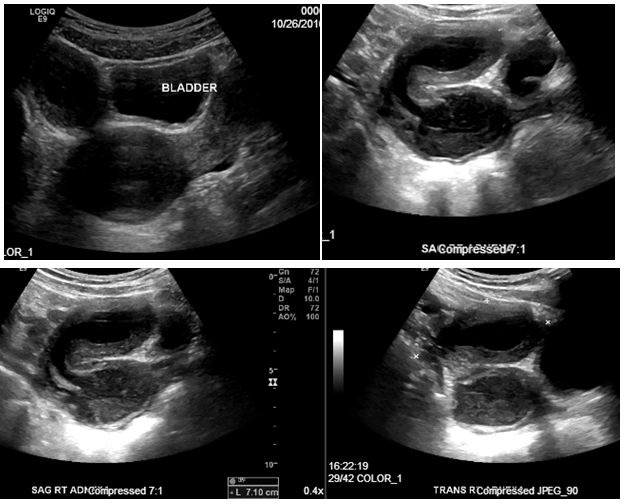

35 years old Hispanic female, G2P2002 with history of two previous cesarean deliveries presented with a retained intrauterine device (IUD). A Para Gard IUD was placed 4 years ago in Mexico and on exam the IUD string could not be visualized. Ultrasound (Figure 6) and MRI (Figure 7) revealed the IUD in the right end cervical canal in the lower portion of the one of her two uteruses. Diagnostic hysteroscopy confirmed the two uterine cavities were not connected to each other and therefore the diagnosis of two separate uteri (didelphys uterus) was confirmed. Further physical examination revealed the patient had a horizontal vaginal septum (Figure 5) with two separate cervices on each side of vaginal septum. Once the retained IUD was clearly visualized in the lower cervix hiding under the vaginal septum it was removed easily with ring forceps.

Figure 6 Patient 2: Pelvic Ultrasound: didelphys uterus with two endocervical canals. The IUD is seen in the right endocervical canal. Patient is still at risk for pregnancy via the patent left cervical canal.

In all three cases pelvic ultrasound was initial imaging tool. The ultrasound in case 1 (Figure 1) and subsequent MRI (Figure 2) shows a lobular tubular thick wall cystic structure in the right pelvis suggesting hemorrhagic contents extending into the right aspect of the posterior vagina and didelphys uterus. MRI of the abdomen depicts renal agenesis, demonstrating abnormal kidney development confirming HWW. As per the classification presented by Zhu and imaging, the patient has a class 1.2 OHVIRA.2 The ultrasounds in cases 2 and 3 (Figures 6 & 9 respectively) both demonstrate didelphys uterus with two cervices. The additional MRI in case 2, revealed two separate cervices and two uteri one with a retained IUD. MDA can be associated with a vaginal septum, more commonly vertical (Case 2 & Figure 5) but cases of a horizontal septum have also been reported (Case 1 & Figure 8).14